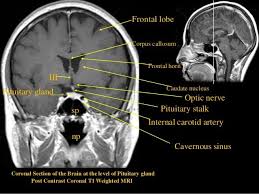

A ct scan uses x rays whereas an mri scan uses strong magnetic fields and radio waves. Ct scans are widely used in emergency rooms because the scan takes fewer than 5 minutes. Mris have no biological hazards but you may be allergic to the contrast dye which make it not suitable for you if you have liver or kidney disorders. An important difference between ct scan and mri is related to the effects they create on the body.

A ct scan uses x rays to create detailed pictures of organs bones and other tissues. Since ct scans use radiation they carry greater risks. What is the difference between a ct scan and an mri. The person lies on a table that moves through a scanning ring which looks like a large doughnut.

Ct scans and mris are both used to capture images within your body. The data collected can be assembled to form three dimensional images.